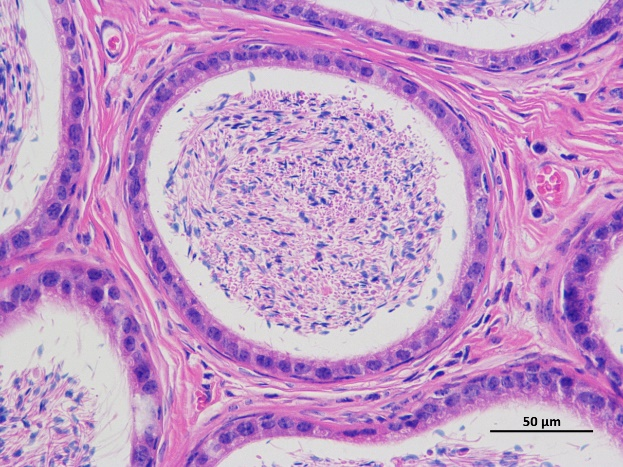

依托标准化实验平台与资深技术团队,我们提供覆盖常规病理、IHC/IF、电镜及生化指标检测的全方位服务,助力疾病机制研究与药效评估。常规病理服务涵盖组织固定、包埋、切片及 HE 染色,呈现精准组织形态学分析;IHC 与 IF 检测支持多靶点共定位,实现蛋白表达与亚细胞定位可视化;电镜服务解析超微结构细节,捕捉纳米级形态特征;生化指标检测覆盖代谢物、酶活性等核心指标,提供定量数据分析